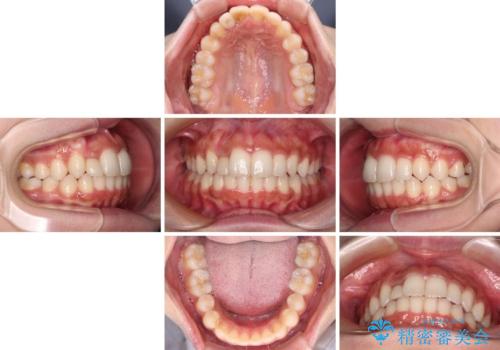

レントゲン写真上では、矯正治療前後で歯根長さに大きな違いはなく、抜歯を回避することができました。

上顎内側に転位している前から2番目の歯は移動が難しく、無理矢理歯根全体を動かそうと設計すると、歯肉退縮・歯髄壊死・歯根吸収といった危険性が増すため、無難なゴールにて治療を終えることとなりました。